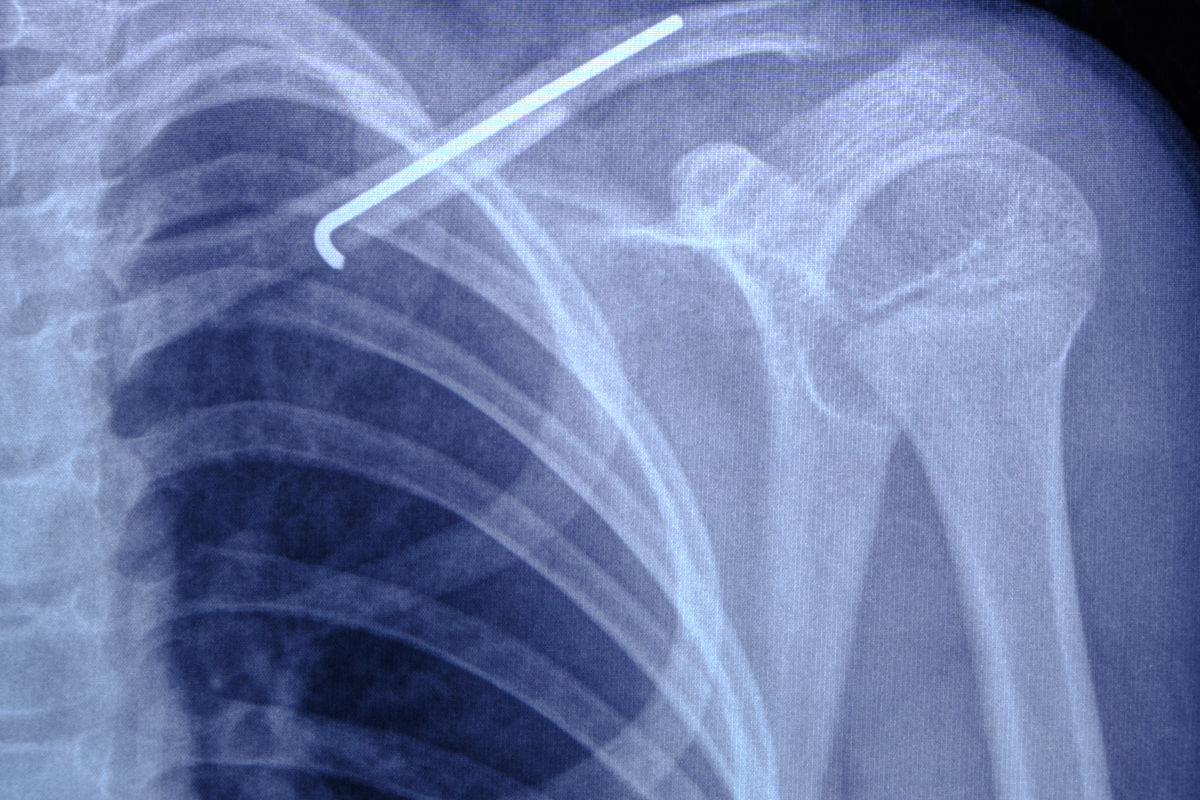

После опроса и осмотра специалист порекомендует больному прохождение аппаратных методов исследования. Чаще всего для диагностики перелома ключицы используется рентгенография. Ее снимки расскажут о точной локализации травмы. Для оценки повреждений близлежащих мягких тканей проводят томографию.

Лечение перелома ключицы

После того, как диагноз был поставлен, врач примется за составление методики борьбы с травмой. Наиглавнейшей составляющей лечения перелома ключицы является ее иммобилизация. Длительность фиксации обычно составляет от трех до восьми недель. В течение этого времени больному следует придерживаться терапевтических требований врача и принимать: